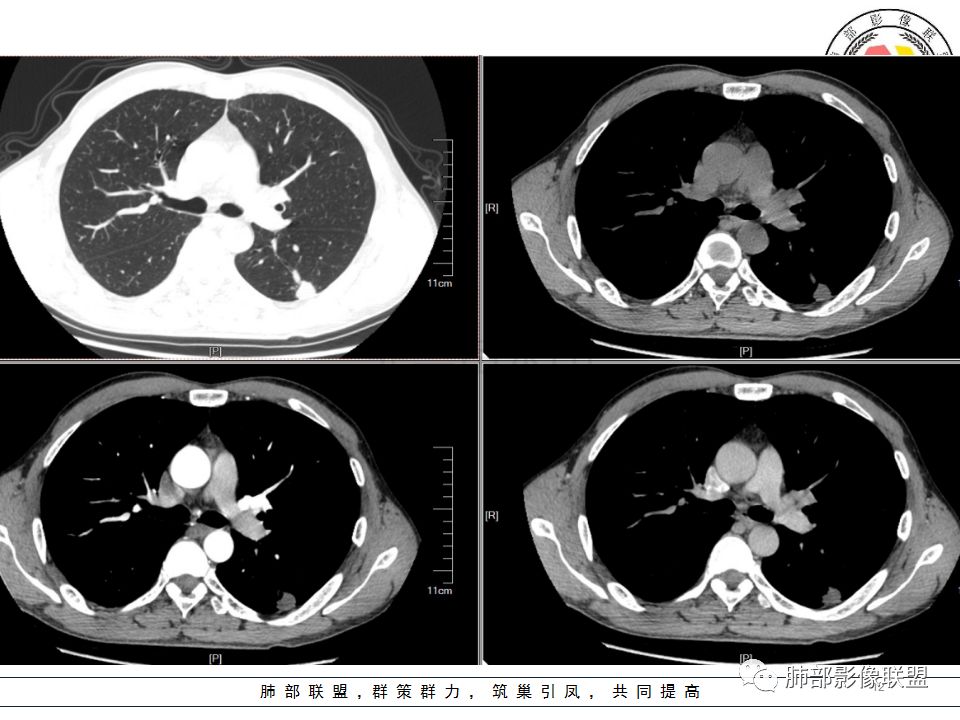

岁月:

我会做一做支气管的CPR,肺动脉的CPR。

因为南边的考虑一定要看到支气管,怎么办呢?

我很早以前做早癌,就是用CPR技术来观看病灶与支气管、血管的关系。

wonderful:

薄层

我的重建图像大部分是这样。

360旋转,可以观看意想不到的效果,我一直很重视这两种重建方法。比想象好 直观。